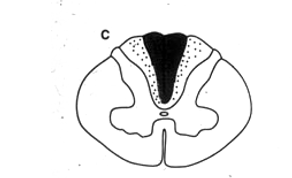

syringomyelia